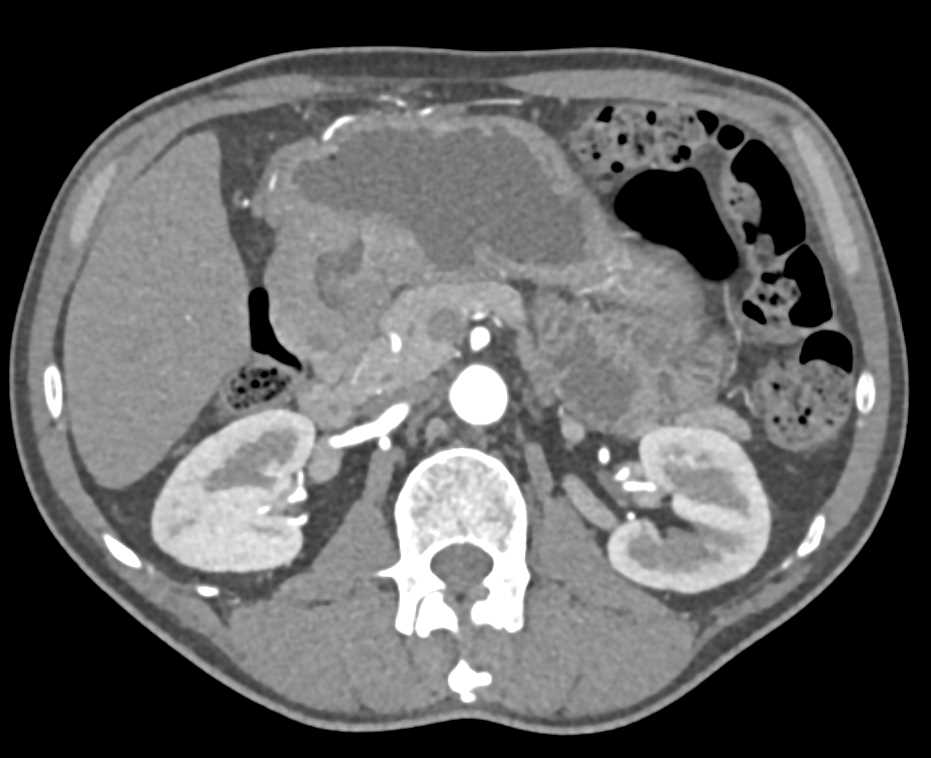

Gastric GIST Tumor